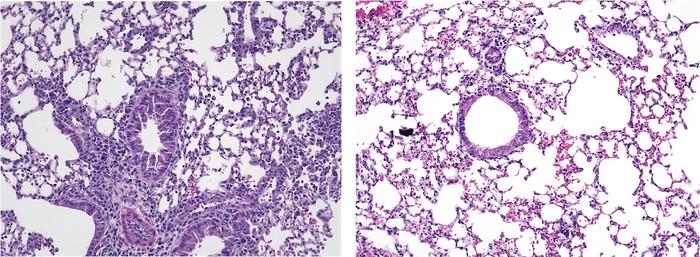

Akbari’s team found that, in the absence of Piezo1, mouse ILC2s became more active than normal in response to allergenic signals, and the animals developed increased airway inflammation. In contrast, treatment with a drug called Yoda1 that switches on Piezo1 channels reduced the activity of ILC2s, decreased airway inflammation, and alleviated the symptoms of allergen-exposed mice. The group’s observations suggest a significant role for Piezo1 channels in ILC2 metabolism, as treatment with Yoda1 reduced ILC2 mitochondrial function and rewired the cells’ energy source.